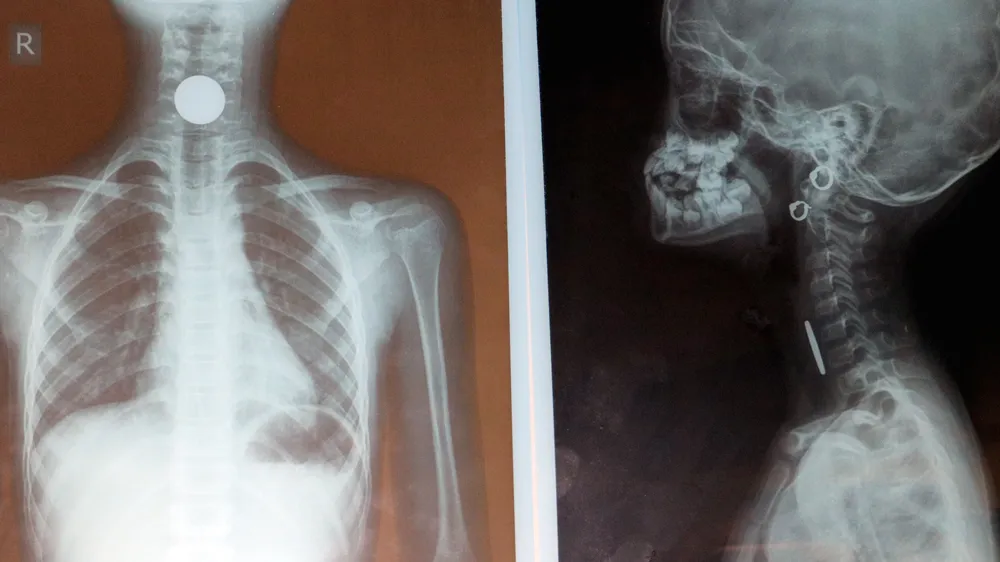

Tại Bệnh viện Đa khoa tỉnh Hà Tĩnh, sau khi thăm khám, làm các xét nghiệm và cho chụp X-quang vùng cổ, các bác sĩ phát hiện có một dị vật cản quang mạnh, hình đồng xu nằm ở vùng cổ bệnh nhân.

Ngay sau đó, khoa Tai Mũi Họng đã chuyển bệnh nhân Ng. lên khoa Gây mê hồi sức để tiến hành soi gắp dị vật. Tại đây, các bác sĩ đã tiến hành gắp ra ngoài thành công một đồng xu có đường kính 2,3cm.

Đồng xu có đường kính 2,3cm được gắp ra ngoài